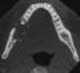

Squamous cell carcinoma of mandible